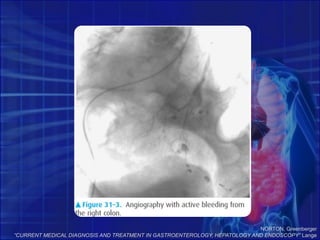

NORTON, Greenberger“CURRENT MEDICAL DIAGNOSIS AND TREATMENT IN GASTROENTEROLOGY, HEPATOLOGY AND ENDOSCOPY” Lange